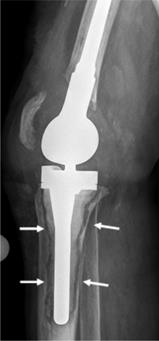

Tissue samples were collected intraoperatively from areas of osteolysis from patients suffering from infectious implant loosening (Figure 1). Patients' clinical data are shown in Table 1. Diagnosis of implant-associated infection was confirmed by histology (>23 neutrophils per 10 high power fields) [25]. H&E staining showed multinucleated giant cells in direct vicinity to surgical suture material. Additionally, immunohistochemical staining for cathepsin K, which is characteristic for osteoclasts, was performed and giant cells in association with suture material showed positive results (Figure 2A-D).

Figure 1

X-ray of a patient suffering from infectious implant loosening of a total knee replacement. Radiolucent lines can be seen particularly around the tibial implant component, indicative of loosening (white arrows).